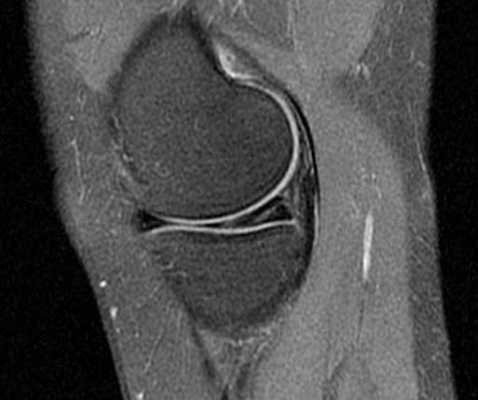

МРТ коленного сустава. Сагиттальная МРТ, отражающая протонную плотность. Нормальная послеоперационная потеря контура сустава.

МРТ коленного сустава. Сагиттальная Т1-взвешенная МРТ. Нормальный ход трансплантата ПКС.